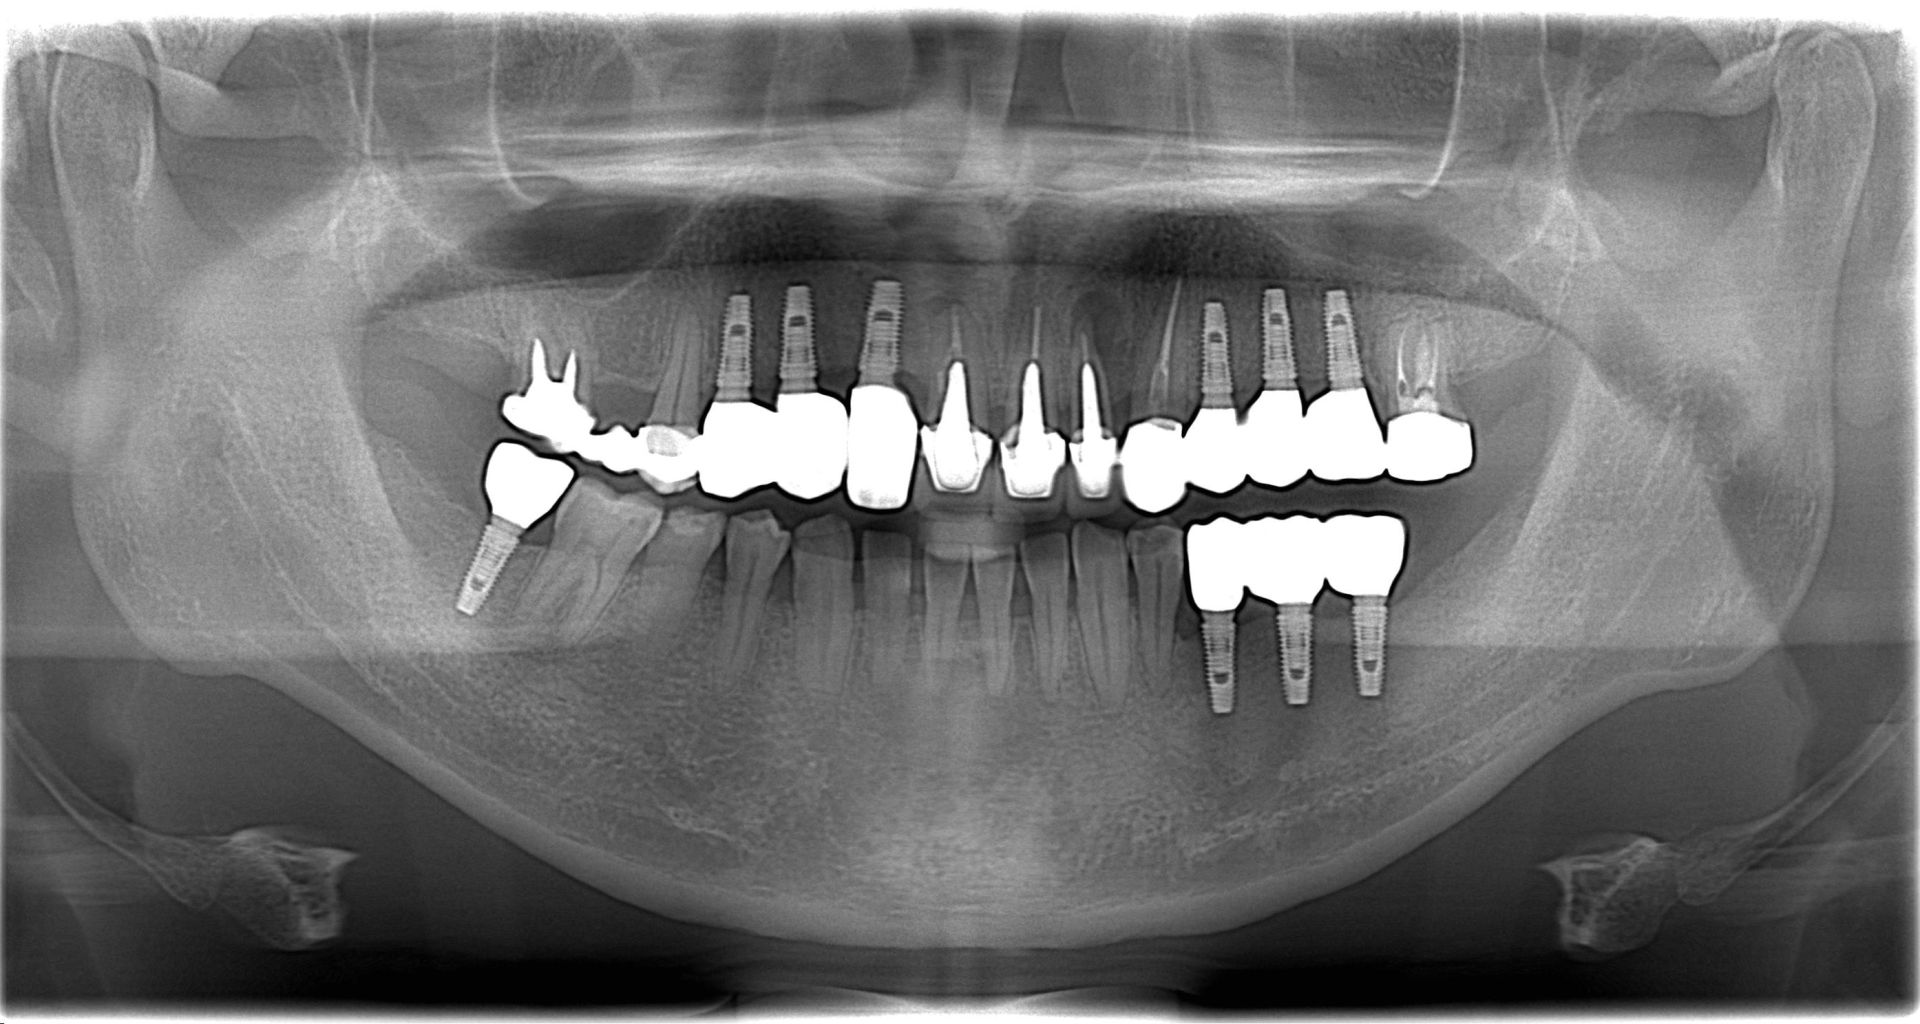

先行口腔內檢查,並結合環口式 X 光片與局部片作綜合判斷。

上顎區域植入了多顆植體,特別是在前牙區與後牙區的配比。

植體牙橋設計: 觀察影像下方,我們利用數顆植體支撐起整片假牙(牙橋設計),這能有效減少手術次數與費用,同時維持極佳的穩定度。

植體的分佈必須考慮到對咬牙的關係,影像中顯示,上下顎的植體位置精準對位,確保咬合力能垂直傳導至骨組織,避免植體鬆脫。